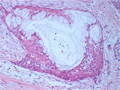

唾液腺腫瘍(粘表皮癌)

ミクロ像(HE弱拡大):腺管や嚢胞状の多数の胞巣を形成している(高分化型)。

• 唾液腺腫瘍(粘表皮癌)ミクロ像(HE弱拡大)